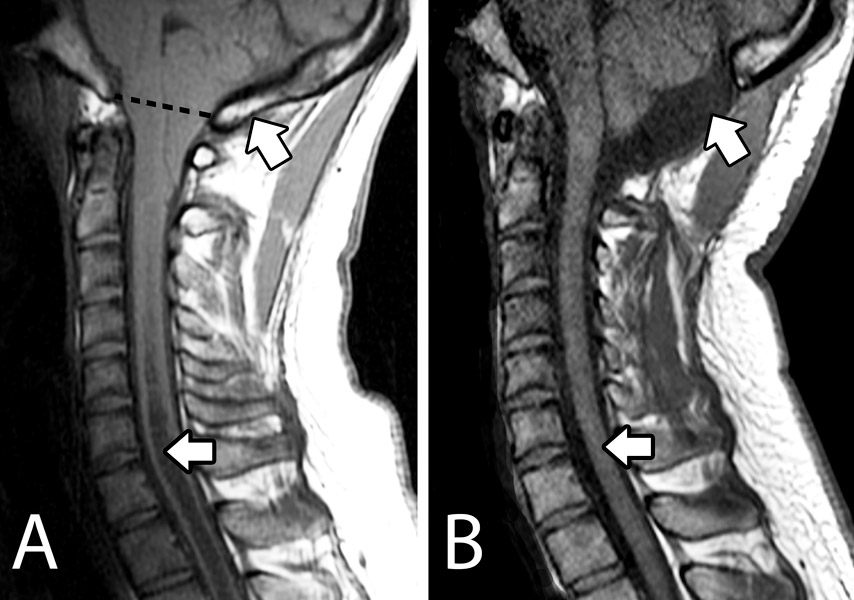

Chiari malformation

is an abnormality in the lower part of the brain called the cerebellum. Most cases of Chiari are congenital, meaning they are present from birth. In an individual with Chiari, the cerebral tonsils hang below the skull opening and into the spinal canal. The degree to which the tonsils extend can vary tremendously. The most common symptom of Chiari malformation is a headache, which begins at the back of the head (neck) and radiates upward. Other symptoms include visual problems; balance difficulties; vertigo and cranial nerve compression, resulting in apnea, swallowing difficulties, syncope or facial numbness. Chiari malformation can cause a fluid collection inside of the spinal cord, known as a syrinx. Some individuals may have hydrocephalus, a buildup of fluid in the ventricles of the brain.

Chiari Shown in Human & Dog MRI